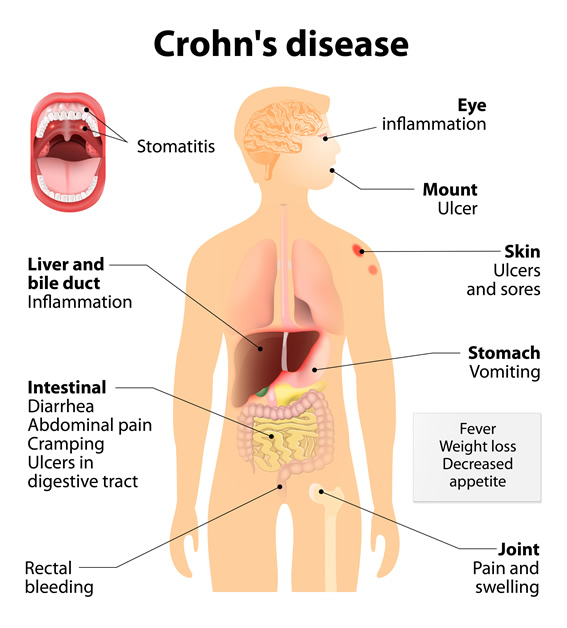

Η νόσος Crohn είναι μια χρόνια φλεγμονώδης νόσος αγνώστου αιτιoλογίας που μπορεί να προσβάλλει οποιοδήποτε σημείο του γαστρεντερικού σωλήνα. Μπορεί, ωστόσο, να προσβάλλει και άλλα όργανα του σώματος, όμως η συνηθέστερη θέση εμφάνισής της είναι ο πεπτικός σωλήνας.

Ωστόσο, η νόσος Crohn μπορεί να εμφανισθεί σε οποιοδήποτε σημείο της εντερικής οδού, δηλαδή από τη στοματική κοιλότητα έως τον πρωκτό και μπορεί να επηρεάσει μία ή και περισσότερες περιοχές. Δεν υπάρχει τρόπος να προβλέψουμε ποιος και πότε θα αναπτύξει τη νόσο Crohn. Πρόκειται για μία χρόνια νόσο που μπορεί να εμφανισθεί ανά πάσα στιγμή, μπορεί να υφεθεί χωρίς εξήγηση και μπορεί να ξαναπαρουσιασθεί έντονα χωρίς προφανή αιτία.

Ως επί το πλείστον η νόσος του Crohn εμφανίζεται είτε στο λεπτό ή/ και στο παχύ έντερο, είτε στην ορθοπρωκτική περιοχή, ή, ακόμη και στις δύο.

Η έναρξη της νόσου και τα συμπτώματα της ποικίλουν ευρέως από ασθενή σε ασθενή. Τα κοιλιακά συμπτώματα μπορεί να περιλαμβάνουν εντερικές κράμπες, πόνο, επίμονες διάρροιες ή δυσκοιλιότητα, αιμορραγία κατά την κένωση, πυρετό, εύκολη κόπωση, αδυναμία και απώλεια βάρους. Αυτό δεν σημαίνει ότι ένας ασθενής θα παρουσιάσει όλα τα συμπτώματα. Συνήθως τα συμπτώματα αυτά χαρακτηρίζονται από χρονιότητα. Σε κάποιες περιπτώσεις η εμφάνιση της νόσου Crohn είναι οξεία και σοβαρή. Η προσβολή μπορεί να είναι τόσο σοβαρή και να εγκαθίσταται με τόσο ταχύ τρόπο, ώστε να επιβάλλεται ακόμη και η άμεση χειρουργική αντιμετώπιση του ασθενούς.